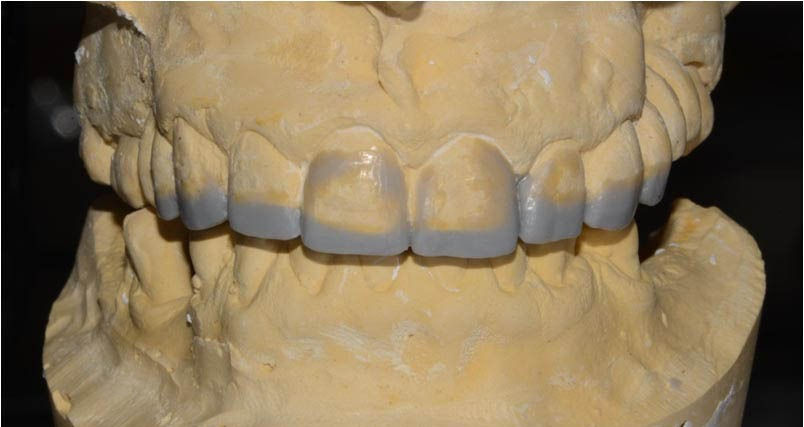

Diagnostic wax-up: the incisal margin is modified to mount the models in centric relation with the maximum intercuspation.

To achieve tooth elongation it is necessary to establish position, length, shape and size starting from the incisal edge of the two central incisors.